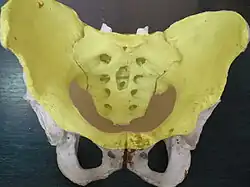

Joints of the pelvis. Anterior view.

Joints of the pelvis. Anterior view. The arteries of the pelvis.